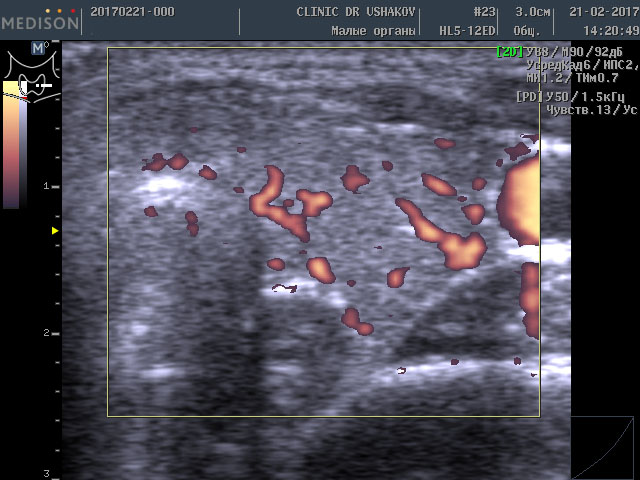

Такое более интенсивное усвоение организмом щитовидных гормонов (Т4 и Т3) вынуждает сильнее заставлять щитовидную железу производить эти гормоны. Избыточная стимуляция происходит с помощью гормона ТТГ (из гипофиза) и шейной части периферической нервной системы. Нервные клетки из нервных центров направляют свои увеличенные стимулы к ткани щитовидной железы, заставляя интенсивнее производить гормоны, и одновременно с такой же силой активизируют кровоток внутри железы, стремясь при этом доставить к ткани железы больше продуктов (для питания и образования гормонов). Вот почему у этой пациентки при УЗИ в нашей Клинике мы выявили умеренное усиление кровотока (рис. 1 и 2). Это заметно на снимках, где в специальном режиме для оценки сосудов (ЭДК) определяется увеличенное количество красных элементов (преимущественно увеличенного размера). Такая картина УЗИ не редко встречается при малом или умеренном гипертиреозе (с тиреотоксикозом), который врачи называют «повышением функции щитовидной железы».

Рисунки 1 и 2. Пациентка В., 32 г. левая и правая доли щитовидной железы в режиме ЭДК. Кровоток умеренно усилен в обеих долях (обозначен красным цветом).

Обратите внимание на активность кровотока по данным УЗИ у этой пациентки (рис. 3 и 4).

Рисунки 3 и 4. Пациентка А., 26 лет левая и правая доли щитовидной железы в режиме ЭДК. Кровоток в малой и умеренной степени усилен (обозначен красным цветом).